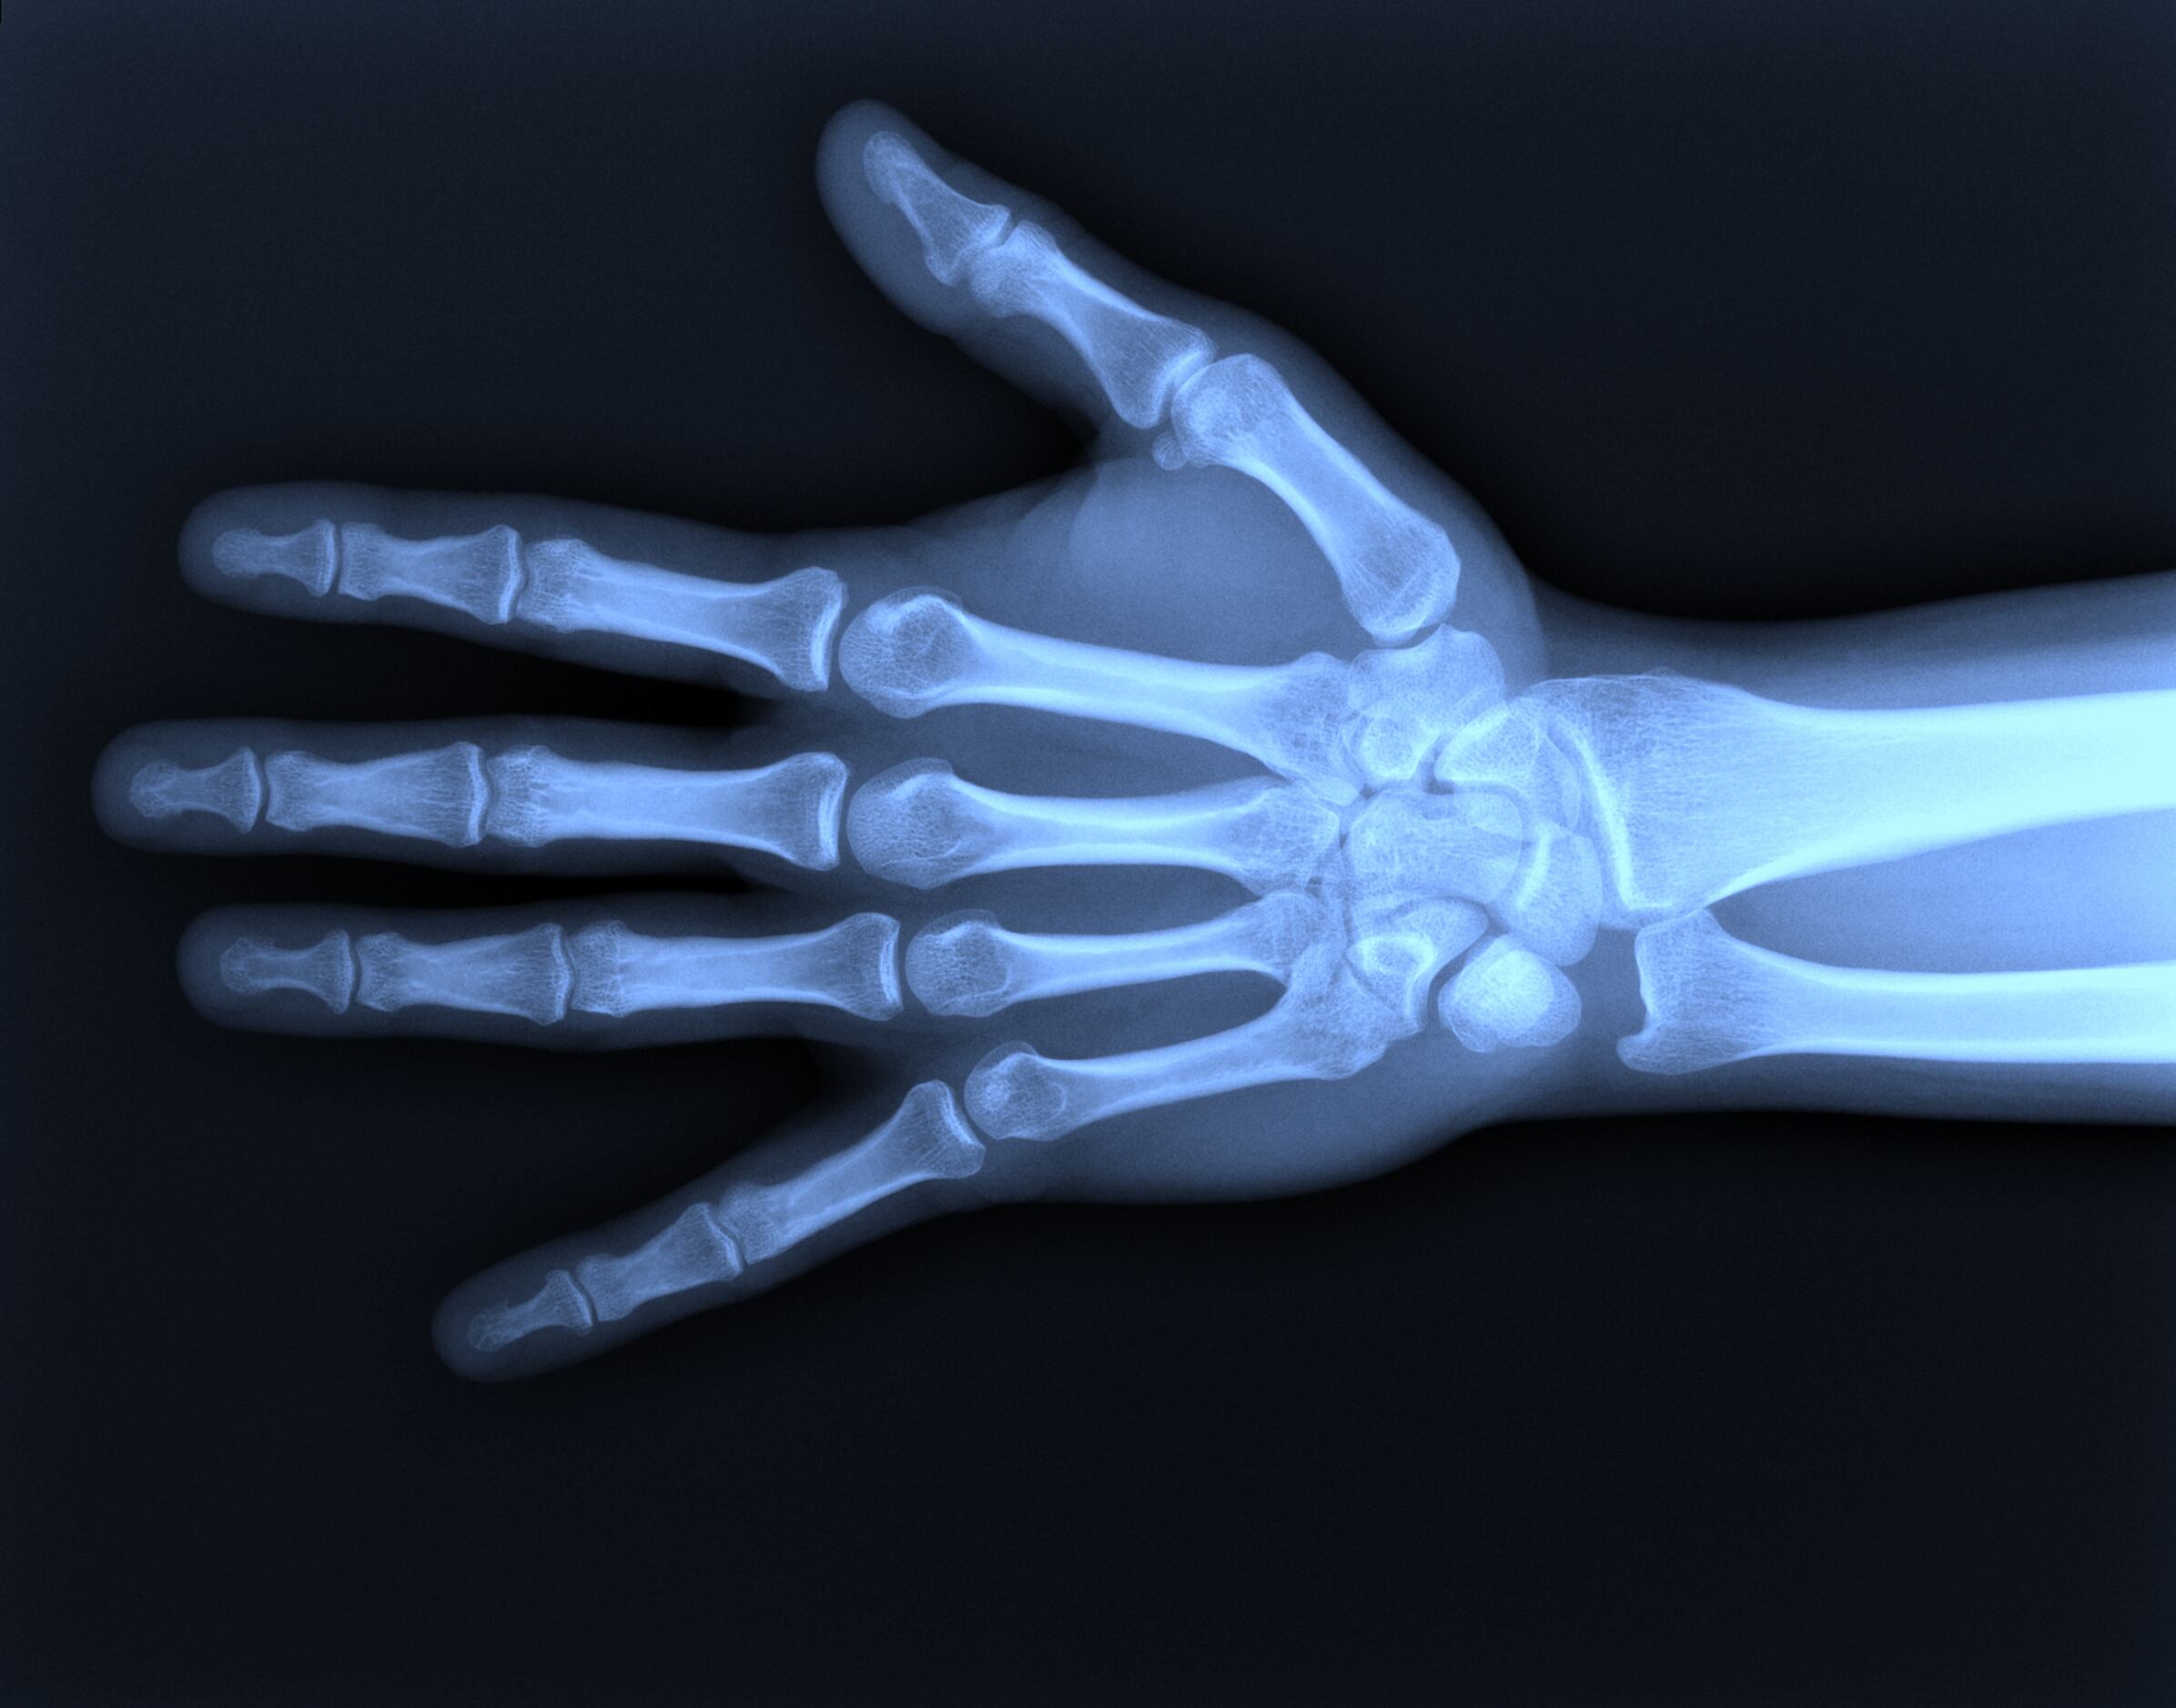

En Costa Rica, especialistas del grupo de Reconocimiento de patrones y aprendizaje automatizado (Parma, por sus siglas en inglés) del Tecnológico de Costa Rica (TEC) trabajan en un proyecto que analiza radiografías para determinar la edad de infantes y desarrollan una aplicación que le permitirá a médicos diagnosticar trastornos de crecimiento.

Los investigadores de Parma usan imágenes de rayos x de la mano izquierda de niños, así como algoritmos para calcular la edad del paciente de acuerdo a estas imágenes. Si el sistema determina que la edad ósea de los infantes no corresponde a la edad real del paciente, eso es una señal clara de que existe un trastorno endocrino o metabólico que está afectando el crecimiento de la persona.

“Que un software pueda tomar una imagen de rayos X y pueda decir cuál es la edad estimada de un niño de meses es muy relevante en medicina, porque si un técnico recibe a un niño, le saca una imagen de rayos X y resulta que el software dice 30 meses, y el niño tiene más o menos esa edad, entonces eso le ayuda a diagnosticar algún problema de crecimiento”, afirma Fabián Fallas, quien trabaja en el TEC y la Universidad de Costa Rica.

Los investigadores del Grupo Parma utilizaron una técnica de inteligencia artificial conocida como deep learning (aprendizaje profundo) para que el programa “aprendiera”, por medio del análisis de una gran cantidad de imágenes, a identificar la edad de los sujetos a los que pertenecen las radiografías.

En este caso los investigadores utilizaron 12.000 imágenes de rayos X de la mano izquierda de hombres y mujeres de entre los 0 y 19 años de edad, tomadas de una base de datos pública que facilitó la Asociación Radiológica de Norte América (RSNA, por sus siglas en inglés).

Los investigadores del TEC y la UCR utilizaron filtros para mejorar la calidad de las imágenes antes de que fueran procesadas. Esto los llevó a mejorar en 42% la efectividad del sistema.